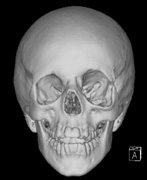

STURGE-WEBER SYNDROME Sturge (1879) reported the case of a child with facial “port-wine stain,” epilepsy, buphthalmos, and a dark choroid.204 Schirmer had noted the association of the facial vascular malformation and glaucoma in 1860.3 Weber (1922) reported brain X-ray findings of parallel streaks (“railtrack” sign), which he interpreted to represent calcific changes (Fig. 19).205

Port-wine stains (PWS) affect 0.3% of live births. The majority of isolated PWS occur in the head and neck.206–208 The possibility of Sturge- Weber syndrome (SWS) is raised when a newborn is noted to have a facial PWS. SWS does not have any clear inheritance pattern. The minimum diagnostic criteria for SWS is a subject of debate.209–211 The complete syndrome includes:

The PWS may not entirely respect the midline, possibly a reflection of transmedian innervation.212 The lesion grows proportionally with the child, often becoming darker in color. 213 The overlying skin may develop nodularity or hypertrophy in two-thirds of patients (by the fifth decade).214 Treatment with a pulsed-dye laser may significantly improve the appearance, but recurrence (i.e., redarkening) is possible.215,216 A deficit in the number of perivascular nerves in port-wine stains suggests that abnormal neural modulation of vascular flow may be involved in their pathogenesis.217 Intracranial leptomeningeal capillary vascular malformation (Figs. 21 and 22) is associated with seizures and contralateral neuromuscular weakness. Central nervous system involvement correlates highly with ipsilateral involvement of the V1 dermatome by a PWS.208,218